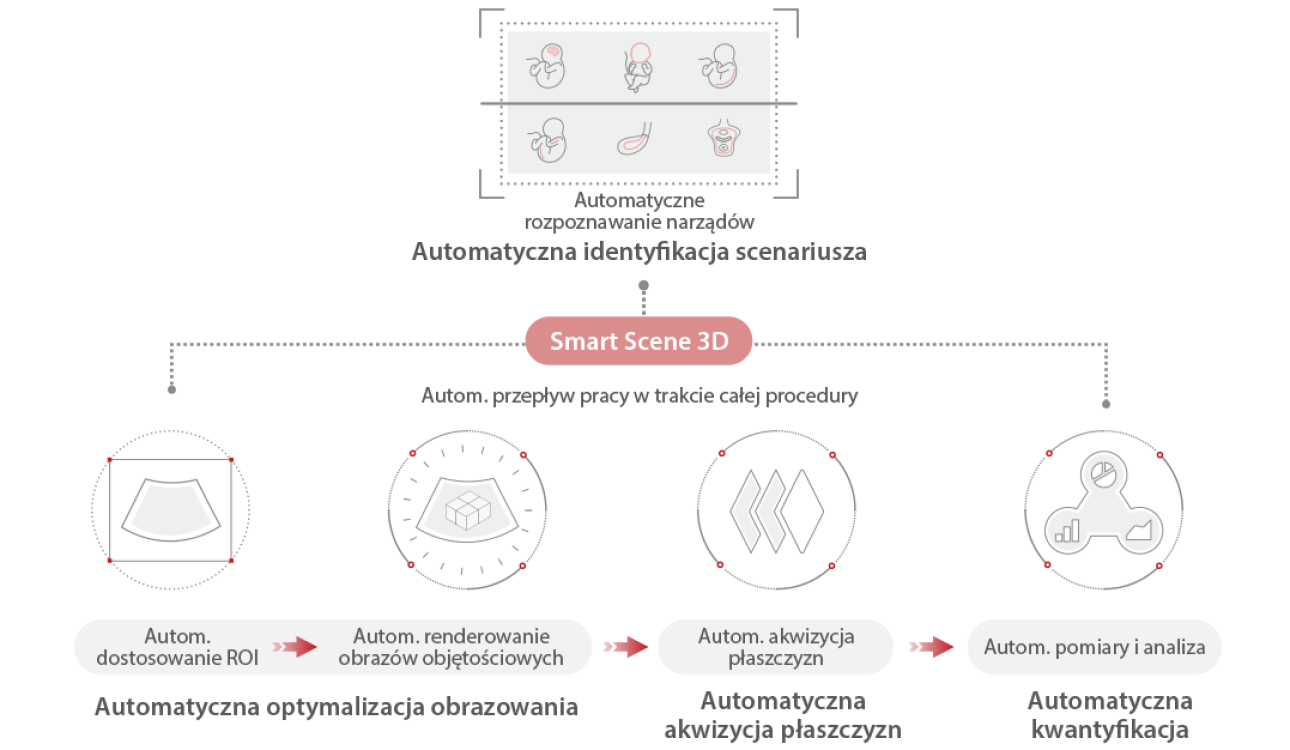

Ultrasonograf Nuewa I9 , zosta? zaprojektowany z my?l? o opiece zdrowotnej kobiet i noworodk├│w. Rozwi?zania zastosowane w Nuewa I9 zosta?y opracowane w oparciu o dog??bn? analiz? r├│?norodnych potrzeb klinicznych, aby zapewni? dok?adn? i szybk? diagnostyk?, a tak?e wyj?tkow? wydajno?? i niezwyk?? wygod? u?ytkowania.